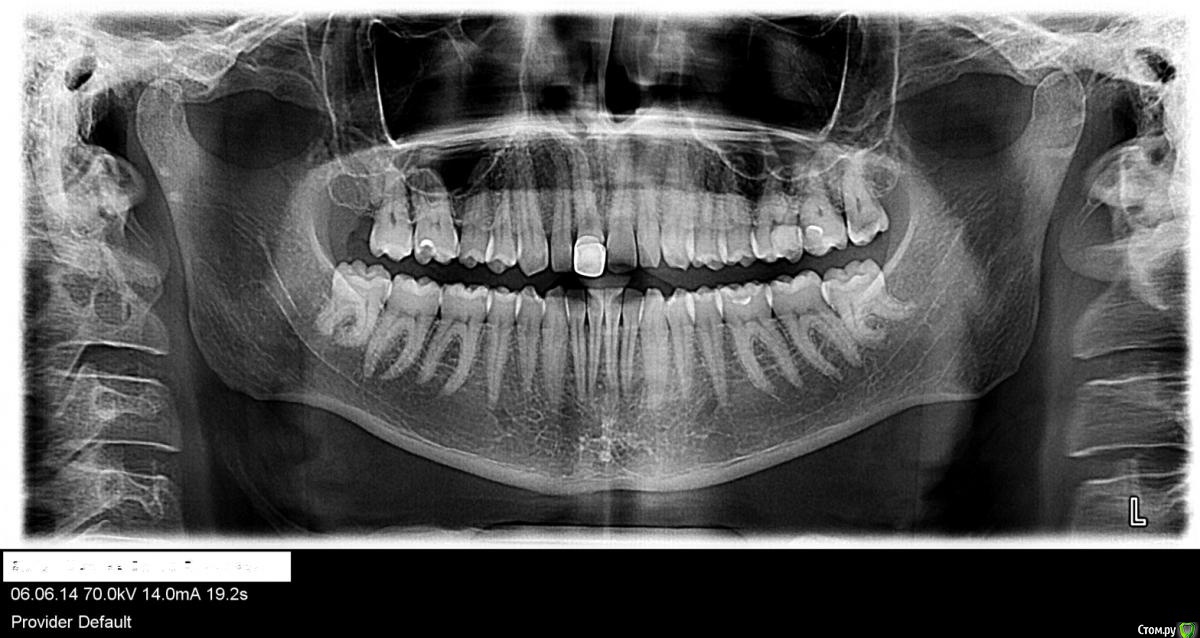

Выкладываю обзорный снимок годичной давности и снимки верхней 6-ки годичной давности, частично там вроде и 7 видно верхнюю левую

post-30402-0-04497700-1431624386_thumb.jpg

post-30402-0-05469600-1431624432_thumb.jpg

Нужен актуальный снимок: возможно, проблема связана с 26 зубом. Если симптоматика будет нарастать, то чисто физически до 24 не дотянете-тогда звоните и записывайтесь с острой болью.

нет сказали что на 27 пломба отошла (глубокий кариес) -см. выше и из-за этого все проблемы - подтекало под пломбу - пульпарная камера рядом что и вызывало болевой синдром и неприятные ощущения.

Не 26 у меня сделан год назад: нервы удалены, каналы пройдены и запломбированы.

да это старые снимки - еще до лечения, вернее во время лечения.

Стоит ли перелечивать 26 зуб если каналы не до конца не запломбированы - чуть чуть верхушки не заполнены , но обработаны полностью

Стоит ли перелечивать каналы если нет никакой симптоматики и не беспокоит этот зуб, так сказать для более лучшего лечения/эффекта ? или лучше не трогать что есть ?